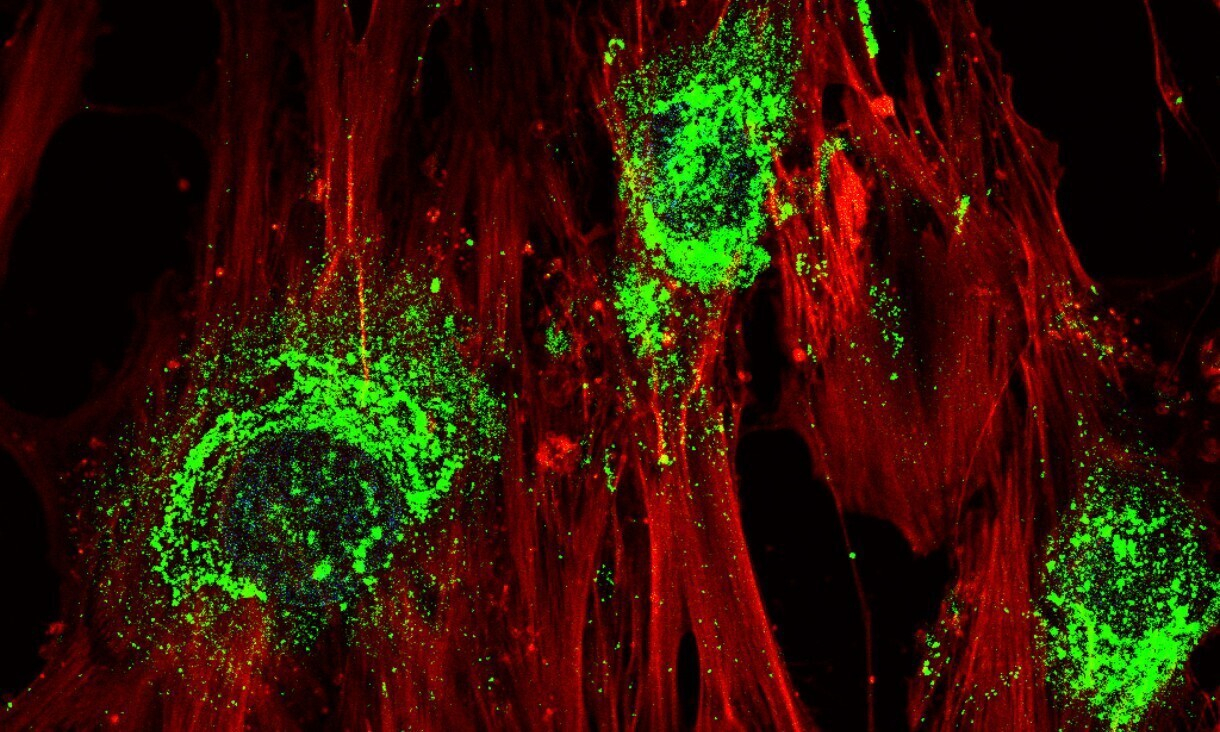

Австралийские ученые при помощи высокочастотного звука вырастили кости из стволовых клеток. Об этом сообщает на своем сайте Мельбурнский королевский технологический университет.

Специалисты взяли стволовые клетки из жировой ткани, поместили их в силиконовое масло и по 10 минут в день в течение 5 суток подвергали воздействию звука частотой 10 мегагерц. Звук создавал микрочип собственной разработки университета. Клетки быстро развились в костную ткань.

Стволовые клетки могут превращаться в любой другой вид клеток, поэтому медицина возлагает на них большие надежды. Ученые ищут новые способы управлять работой стволовых клеток.